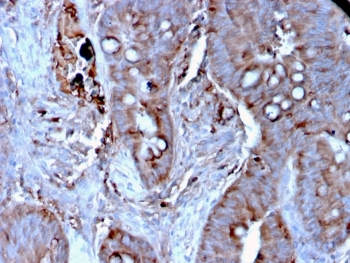

IHC staining of FFPE human colon carcinoma tissue with MERTK antibody (clone MERTK/3024). HIER: boil tissue sections in pH 9 10mM Tris with 1mM EDTA for 20 min and allow to cool before testing.